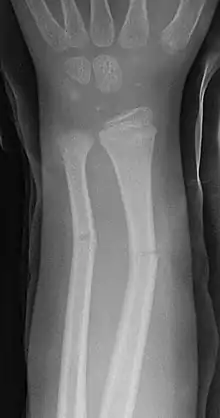

Fractura en tallo verde

En medicina, se denomina fractura en tallo verde a un tipo de fractura ósea propia de los niños. Afecta a la región central (diáfisis) de los huesos largos, sobre todo en el antebrazo. La denominación en tallo verde procede de la analogía entre este tipo de fractura y la que se produce al intentar romper el tallo verde de una planta.

Se caracteriza por ser una fractura incompleta, con ruptura del periostio y la cortical en el lado de la convexidad del hueso, mientras que en la zona cóncava el periostio no llega a romperse, como consecuencia el hueso no está totalmente roto (fractura incompleta), pero los fragmentos se desplazan y presentan una angulación de amplitud variable que es preciso corregir. [1][2]

Las fracturas en tallo verde afectan por lo general a la porción central o diáfisis de los huesos largos de los niños, sobre todo a la región del antebrazo, muñeca y clavícula. Raramente se produce en otros huesos como la tibia y el fémur. Cuando afecta al antebrazo puede existir fractura del cúbito, el radio o ambos huesos simultáneamente.